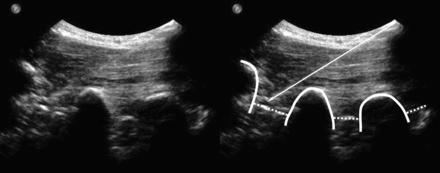

A spinal needle (21-ga, 80-mm; Sterican; Braun, Kronberg, Germany) was then inserted with an in-plane technique (needle advanced strictly parallel to the long axis of the transducer at an angle of approximately 45°, which enables real-time visualization of the entire needle path) (Fig 1). The needle was advanced until the targeted segmental intertransverse ligament was penetrated by the needle tip and thus, the orifice of the needle had reached the pararadicular compartment. To evaluate accuracy, a CT scan controlled this final needle position (Somatom Sensation Open; Siemens, Erlangen, Germany). First, a topogram centered on the needle tip was made for control of the correct spinal segment, and axial sections were obtained for control of needle tip position. If the needle diverged from the intended target position, it was replaced under US guidance. Once the needle was positioned correctly, the elapsed time for the procedure was recorded and 1-mL of betamethasone (4 mg) was injected into the pararadicular compartment.

US sagittal paravertebral scan at the PAP: pararadicular injection at the level L2-L3 (left image) and annotated scan (right image). The thick line indicates the transverse processes; dotted lines, intertransverse ligaments; arrow, injection needle.